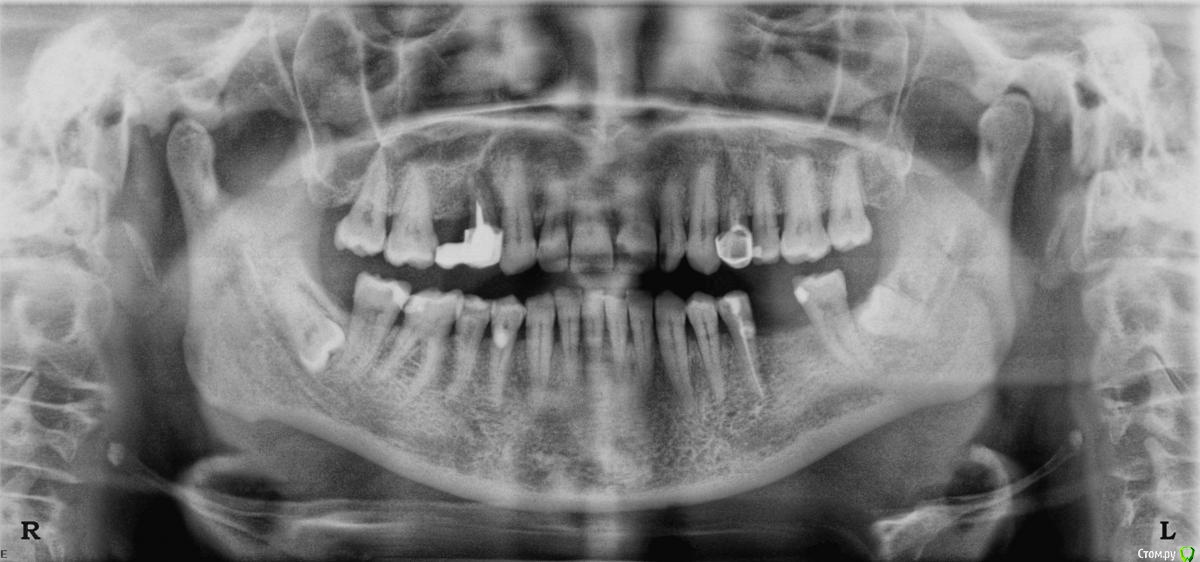

INDEX Опубликовано 31 марта, 2016 Автор Поделиться Опубликовано 31 марта, 2016 Добрый день.Для того ,что бы сделать снимок нужно направление от врача,направили на панорамный снимок,т.к. визиографию не делают.Сказали,что у меня периодонтит ,значительное убывание костной ткани.Посмотрите,какие зубы нуждаются в перелечивании,т.к многие пломбы стоят долгое время. Ссылка на комментарий